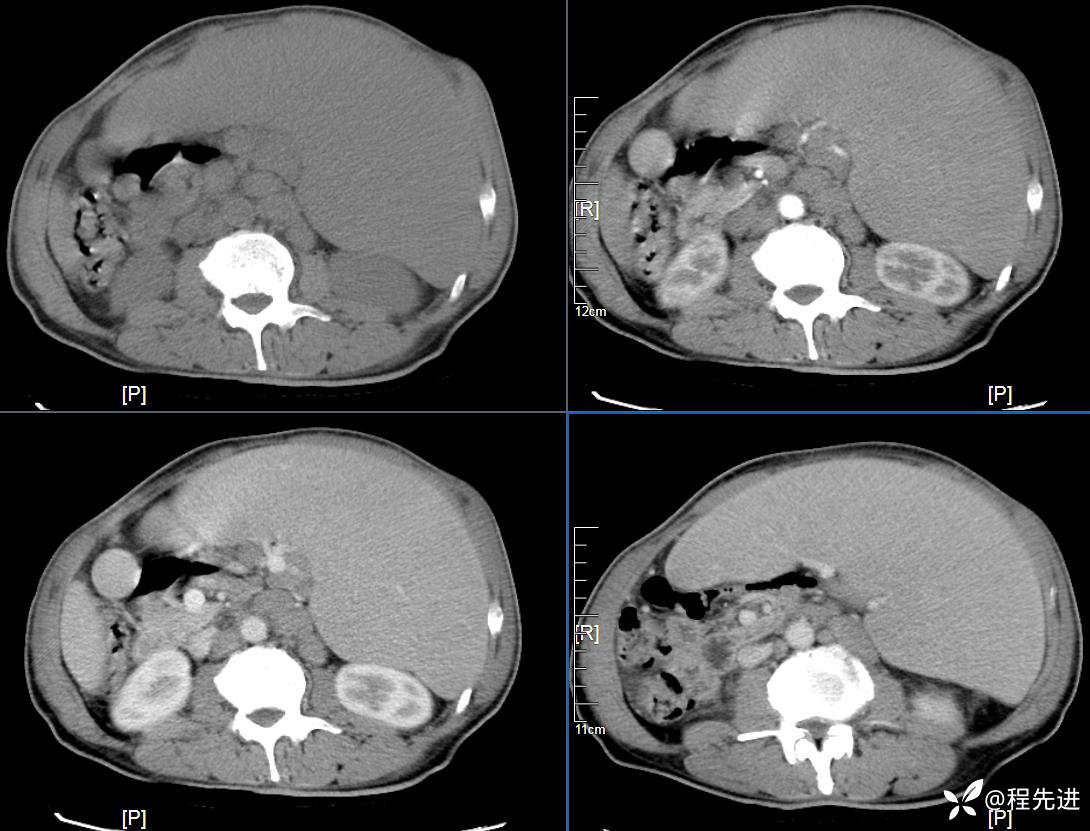

CT平扫及增强3期: